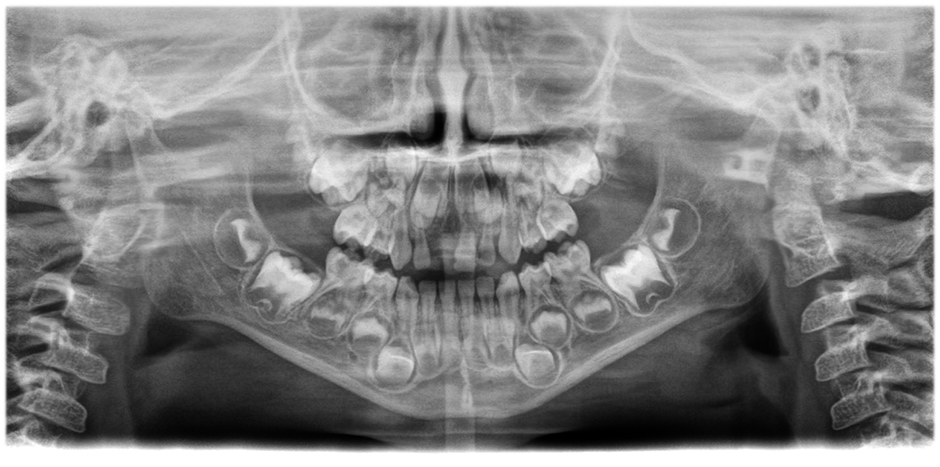

• Panoramabilder von herausragender Klarheit und Schärfe

mit dem innovativen 21-Layer-Autofokussystem, das nahtlos in eine Patientenpositionskorrektur integriert ist.

Bewegen Sie den Slider, um den Unterschied zu sehen (linkes Bild ohne, rechtes Bild mit Autofokus und korrigierter Patientenposition).